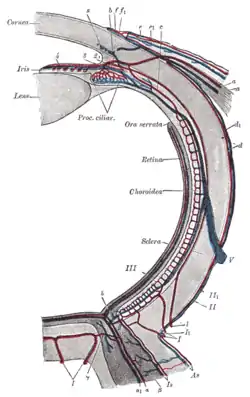

Diagram of the blood vessels of the eye, as seen in a horizontal section. (Central retinal vein not labeled, but region is visible. The central retinal vein is at bottom running away from the retina through the optic nerve.) | |

The central retinal vein (retinal vein) is a vein that drains the retina of the eye. It travels backwards through the centre of the optic nerve accompanied by the central retinal artery before exiting the optic nerve together with the central retinal artery to drain into either the superior ophthalmic vein or the cavernous sinus.

The central retinal vein is formed by the convergence of veins that drain retinal tissue. The central retinal vein originates within the eyeball, emerging from the eyeball already as a single unified vein.[1]

The central retinal vein runs through the centre of the optic nerve (alongside the central retinal artery) surrounded by a fibrous connective tissue envelope.[2] It leaves the optic nerve 10 mm from the eyeball along with the central retinal artery, also exiting the meningeal envelope of the optic nerve.[1]

The central retinal vein drains into either the superior ophthalmic vein or the cavernous sinus.[1]